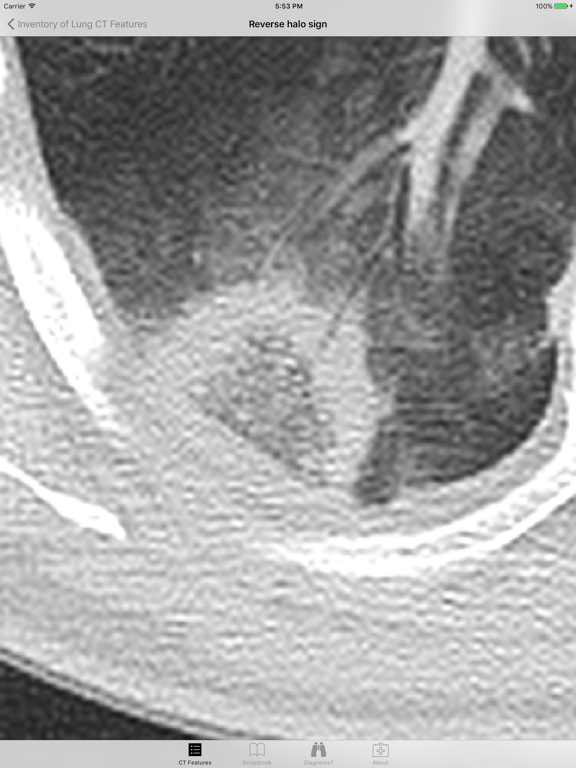

Introducing the Lung CT Field Guide app, an excellent resource for a wide-range of physician specialists, in particular radiologists and pulmonologists. One of the critical steps in interpreting a lung CT is identifying and appropriately describing imaging findings in the lung. Review and explore lung CT images and color graphic illustrations of the fundamental patterns of lung disease on CT. Play with an experimental diagnosis engine that will try to suggest a differential diagnosis list to consider with any number and combination of lung CT findings! Includes over 100 carefully curated CT images and color graphic illustrations.

· Over 60 prototypical lung CT images, organized by: increased attenuation findings, decreased attenuation findings, miscellaneous findings, craniocaudal distribution, and axial distribution

· Nearly 60 color graphic illustrations of prototypical lung CT imaging features